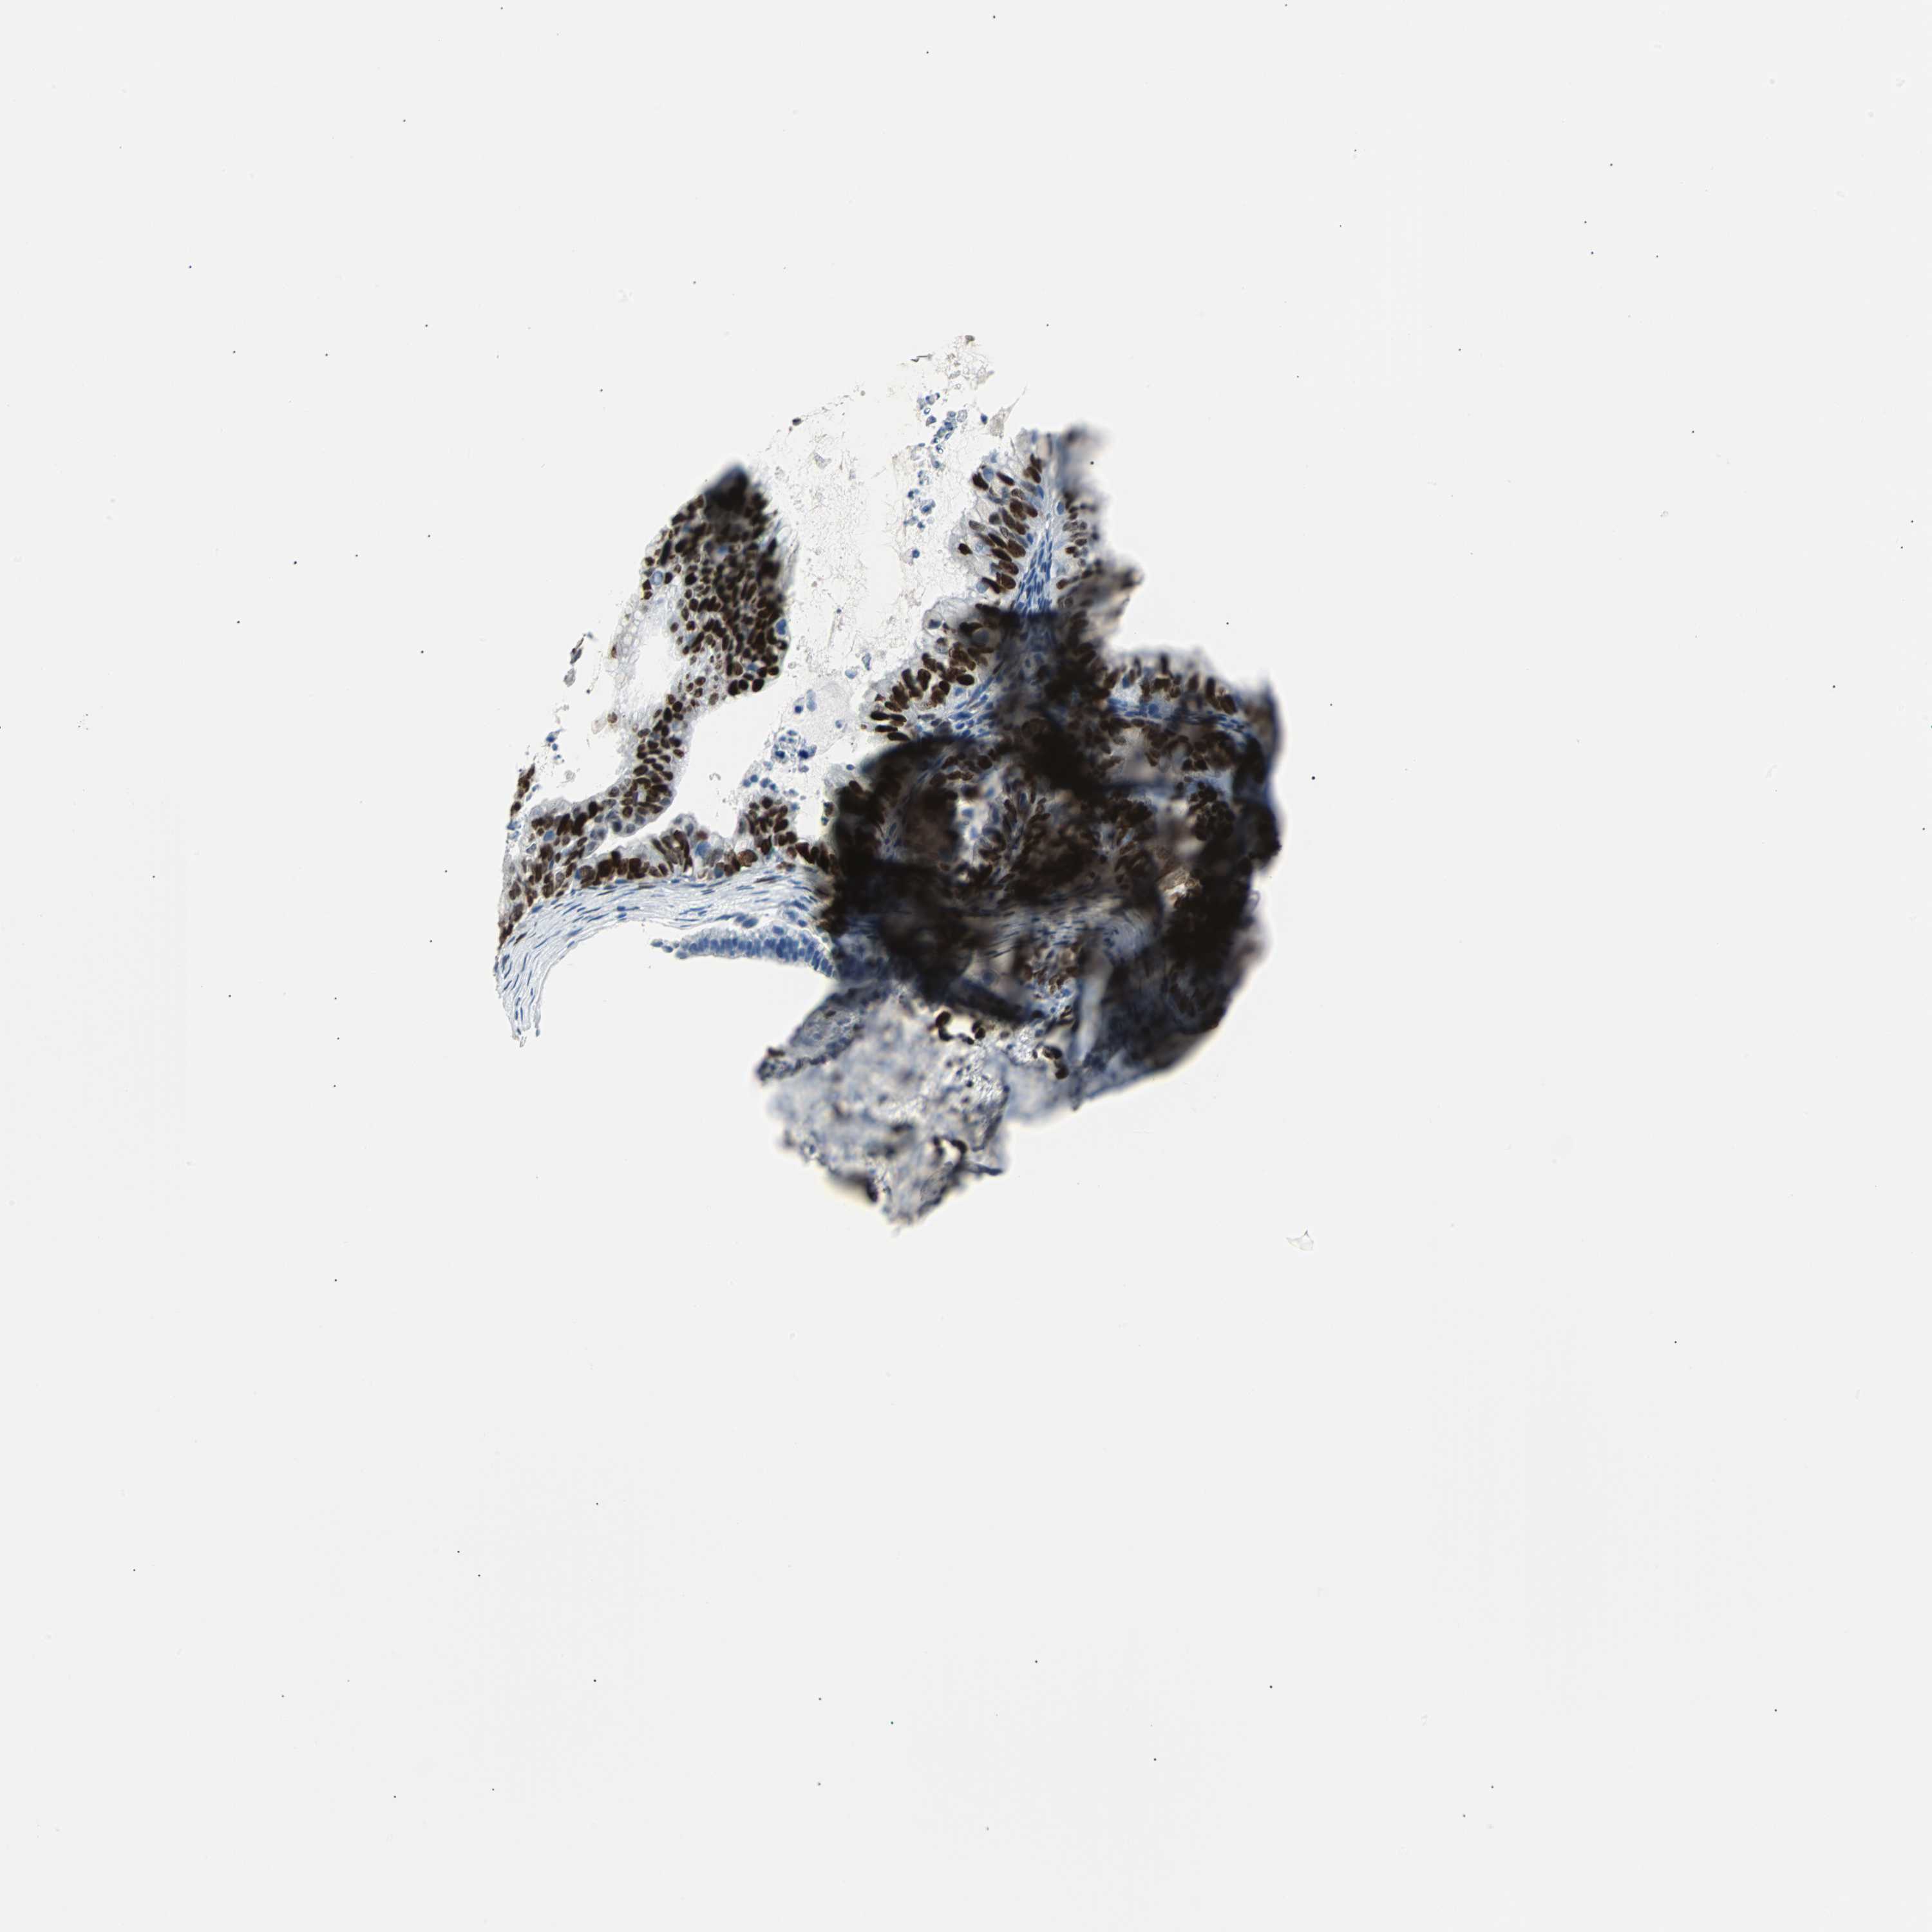

OVARIAN CANCER - Protein expressioni

A mouse-over function shows sample information and annotation data. Click on an image to view it in a full screen mode. Samples can be filtered based on level of antibody staining by selecting one or several of the following categories: high, medium, low and not detected. The assay and annotation is described here.

Note that samples used for immunohistochemistry by the Human Protein Atlas do not correspond to samples in the TCGA dataset.

Antibody stainingi

Antibody staining in the annotated cell types in the current human tissue is reported as not detected, low, medium, or high, based on conventional immunohistochemistry profiling in selected tissues. This score is based on the combination of the staining intensity and fraction of stained cells.

Each image is clickable and will lead to virtual microscopy that enables deeper exploration of all samples and also displays staining intensity scores, fraction scores and subcellular localization as well as patient and tissue information for each sample.

Antibody HPA024426

Antibody CAB007057

Cystadenocarcinoma, serous, NOS